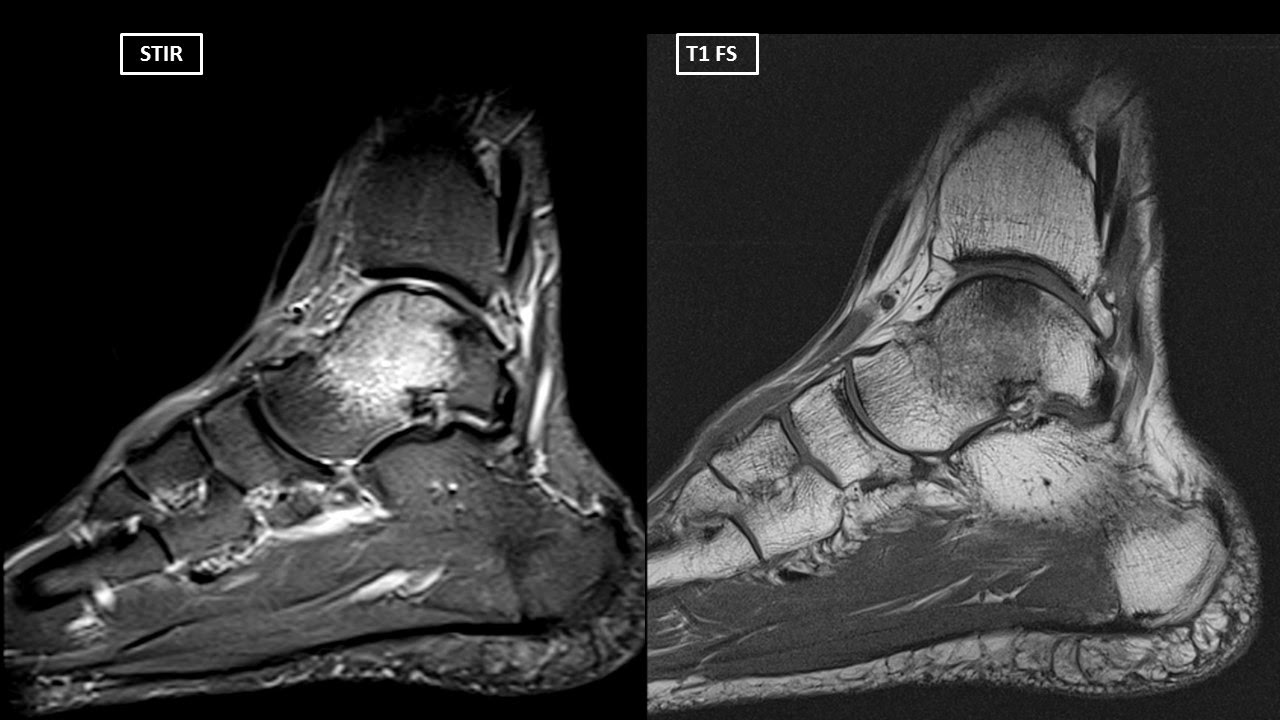

a. MR imaging indicated bone marrow edema of the proximal tibia, distal

Be Aware of Bone Marrow Edema Syndrome in Ankle Arthroscopy: A Case

Source: www.arthroscopyjournal.org